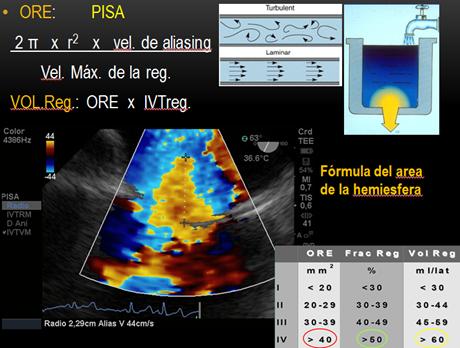

Analizamos la vena contracta (el orificio fisiológico de la regurgitación, es el cuello o la parte más estrecha del jet distal al orificio regurgitante), IM leve < a 3mm y severa mayor a 7mm. Luego el orificio regurgitante efectivo y el volumen regurgitante por los métodos de convergencia del flujo o área de la superficie de isovelocidad proximal (PISA) y de cuantificación(21) PISA(22) se basa en un principio hidráulico, donde la sangre que se aproxima a un orificio circular va formando capas concéntricas de isovelocidad creciente y superficie decreciente. En condiciones ideales, en un orificio circular pequeño sobre una superficie plana, estos contornos de isovelocidades tienen una forma hemiesférica. Por el principio de continuidad, el flujo en cada uno de estos contornos es igual, y a su vez igual al flujo a través del orificio valvular. Si podemos calcular el área de cualquiera de estos contornos y estimar su velocidad podemos calcular el flujo (flujo=Area x velocidad) (Figura16). Si la forma de los contornos de isovelocidad es hemiesférica entonces:

La velocidad de la hemiesfera, la obtenemos del mapa color donde ocurre el primer aliasing.

Ajustamos la velocidad de aliasing, para poder ver la hemiesfera circular y asumiendo que el máximo radio de esa hemiesfera coincide con la máxima velocidad de la IM, se puede calcular el orificio regurgitante efectivo con la siguiente fórmula:

Donde Va es la velocidad de aliasing y la Vreg pico, es la velocidad pico de la IM tomada con Doppler continuo. Y cuando ORE es mayor de 0.4 cm2 es IM severa y ORE menor de 0.2 cm2 es leve.

A partir del ORE calculamos el Volumen Regurgitante (VR):

Donde IVT, es integral velocidad tiempo en este caso del jet regurgitante. VR, mayor de 60ml y de 30ml es grave para las IM orgánicas y funcionales respectivamente.